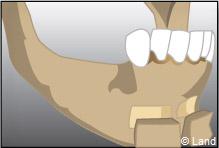

LES GREFFES D’APPOSITION

Elles sont indiquées dans les insuffisances d’épaisseur.

Les différentes étapes :

Prélèvement du greffon au niveau du site donneur